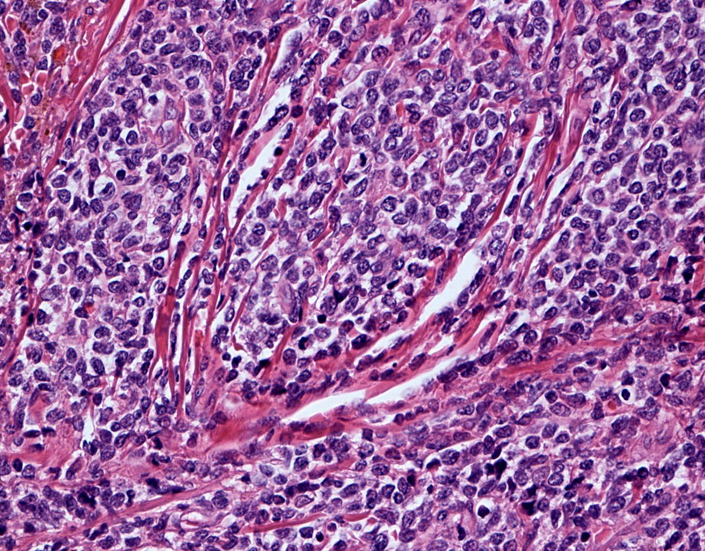

罹患リンパ節の基本構造は消失し腫瘍細胞のびまん性増殖で置換されている。非腫瘍性の小リンパ球(CD3+, CD4/8+)が濾胞様に散在して残る(Fig.01)。不整型または類円形の明るい核をもつmedium-sizeのリンパ球様細胞が密に増殖している。細胞質は乏しい(Fig.02)。CD68陽性macrophageが多く混在する部分が認められた(Fig.03)。

Fig04, Fig05は腫瘍細胞の拡大像。大型異型細胞の出現が認められる。腫瘍細胞はCD4+, CD56+, CD123+(Fig.06)

tcells02.jpg